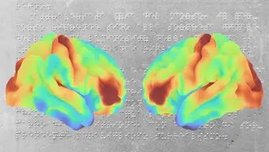

Wie entwickelt sich das Gehirn eines Menschen, der noch nie gesehen hat? Mithilfe modernster bildgebender Verfahren untersuchte ein polnisch-deutsches…